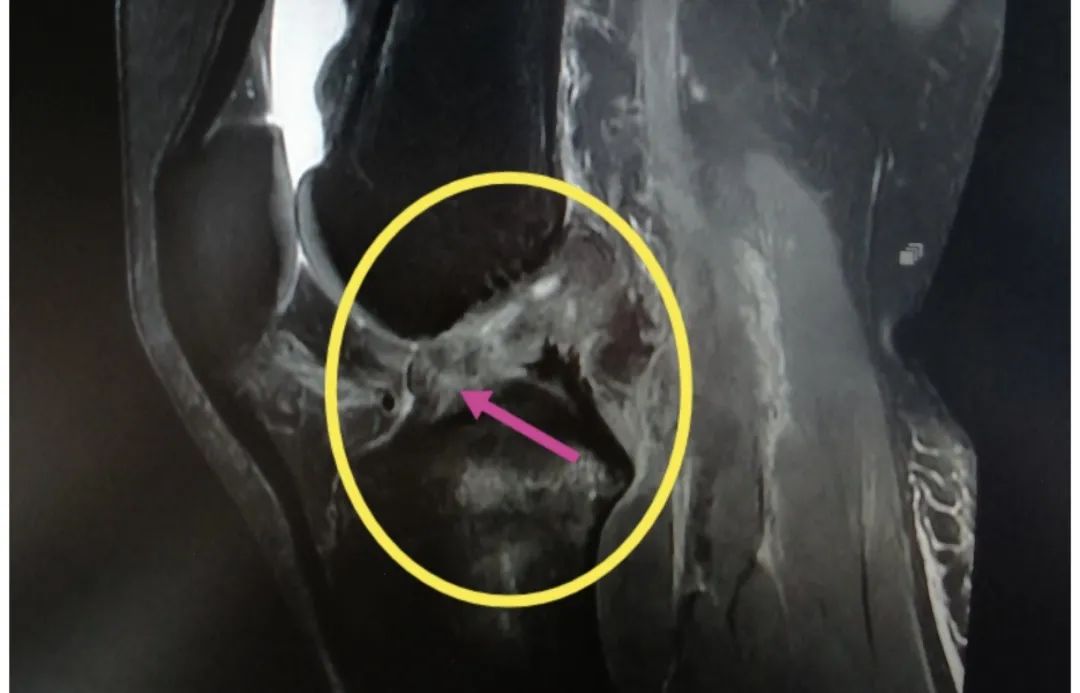

近期,同仁医院骨科程千主任团队就收治了数十例前交叉韧带断裂的病人,他们大多数是爱好运动的年轻人,不适当的运动导致了前叉韧带断裂。

前交叉韧带的主要功能是限制胫骨前移,其次是控制膝关节过伸、旋转。当运动时突然改变方向,膝关节「啪」地一声,之后就会出现肿胀,随之而来的是膝关节不稳或「打软腿」。这个时候你有可能就中招了。

几乎所有急性 ACL 损伤的患者都有关节积液,有时候还会伴有其他韧带、半月板、关节软骨、软骨下骨挫伤等。